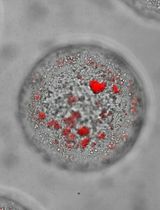

Diverse in vivo animal models have been established to study bone metastasis. Intracardiac injection has been utilized as the gold standard to develop bone metastasis by injecting cancer cells into the left ventricle in mice, with a goal of recapitulating the bone metastasis process, including cancer cell survival in the bloodstream, extravasation, cancer cell arrest in bone, and bone metastatic tumor growth (James et al., 2015). Similarly, intracaudal arterial injection was established to provide an easy-to-use model with higher efficiency of bone metastasis (Kuchimaru et al., 2018). However, the intratibial injection model is used to mimic the scenario when cancer cells have metastasized to the bone, thus providing a better focus on the crosstalk between cancer cells and the bone microenvironment. Herein, we will focus on tibial tumorigenesis by using the intratibial injection model to mimic the setting of cancer patients who have developed bone metastasis.

In this protocol, we take the prostate cancer cell line PC-3 as an example, describe the hands-on procedures of cell preparation, intratibial injection, monitoring tibial tumor growth, and post tissue collection analyses, highlight the critical steps in cell preparation and intratibial injection, and detail how to quantitatively analyze the tibial tumors in histological samples.